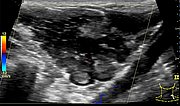

B-scan ultrasonography (longitudinal section) shows the venous malformation to be relatively homogeneously hypoechoic to anechoic. The venous dysplastic vascular channels are compressible with the ultrasound transducer and contain liquid blood.

B-scan ultrasonography (cross-section) also shows the venous malformation as combined hypoechoic to anechoic. The more echogenic parts correspond to sections of the venous malformation in which the contained blood has already clotted. In the anechoic portions, the contained blood is still liquid. In addition, a small phlebolith is found in the lesion, which is practically pathognomonic for a venous malformation.